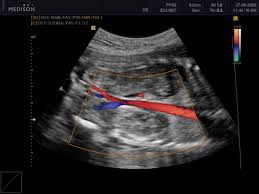

Цветовое доплеровское картирование проводиться для исследования кровотока средних и крупных сосудов, в редких случаях мелких сосудов. Полученная информация выводиться на монитор и представляется графически. Красным цветом на изображении кодируется поток, который направленный в сторону датчика, синим цветом кодируется поток, направленный в сторону от датчика. Оттенки цветов могут варьироваться,  и оттенок цвета зависит от скорости кровотока. В метах с медленным кровотоком цвет проявляется темным оттенком, в местах с быстрым – светлым.  Места с препятствием нормальному кровотоку кодируются зеленым, синим или желтым цветом. Цвета также показывают направление тока крови в исследуемом участке.